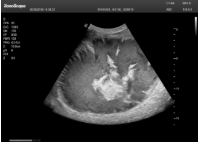

1單晶體凸陣探頭

采用了單晶體探頭材料,探頭面是凸面,接觸面小,成像視野呈扇形,應(yīng)用廣泛,常應(yīng)用于腹部、婦產(chǎn)、肺部等相對部位較深的臟器。

肝癌